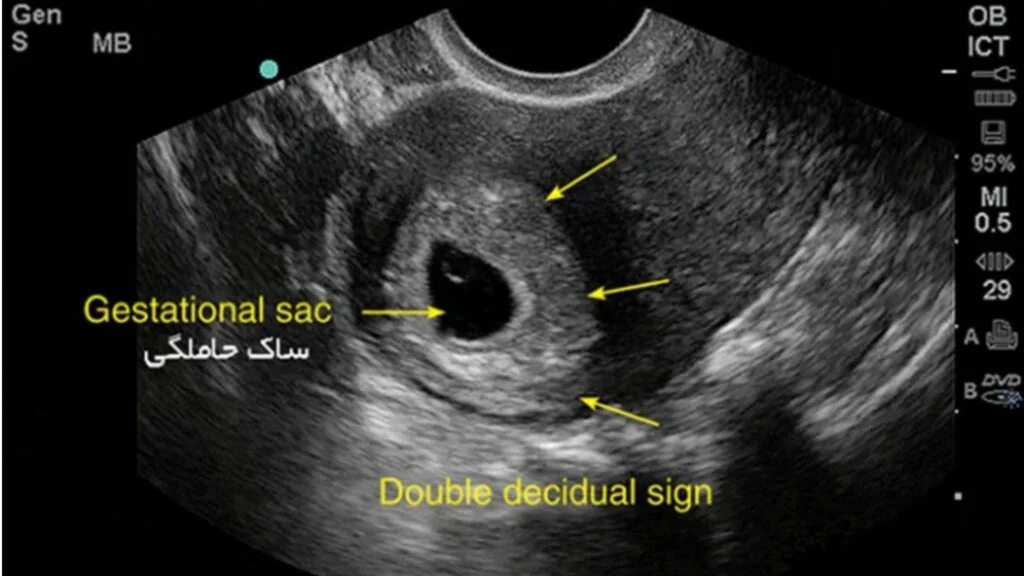

از کجا بفهمم بارداریم پوچ نیست؟

از کجا بفهمم بارداریم پوچ نیست؟ بارداری پوچ یکی از اتفاقاتی است که میتواند باعث نگرانی زیادی در خانمها شود. بارداری پوچ زمانی رخ میدهد که لقاح انجام شده اما جنین تشکیل…

از کجا بفهمم بارداریم پوچ نیست؟

از کجا بفهمم بارداریم پوچ نیست؟ بارداری پوچ یکی از اتفاقاتی است که میتواند باعث نگرانی زیادی در خانمها شود. بارداری پوچ زمانی رخ میدهد که لقاح انجام شده اما جنین تشکیل…